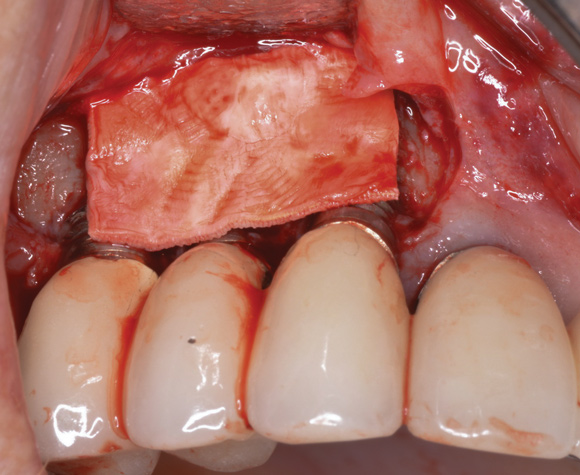

(17.) A cross-linked collagen bone graft scaffold is applied over the debrided implant surfaces to help reconstruct a portion of the deficient buccal bone.

Figure 17